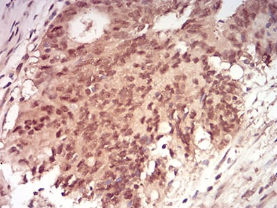

RAN Mouse Monoclonal antibody[8D1H1]

IHC    1/200 - 1/1000